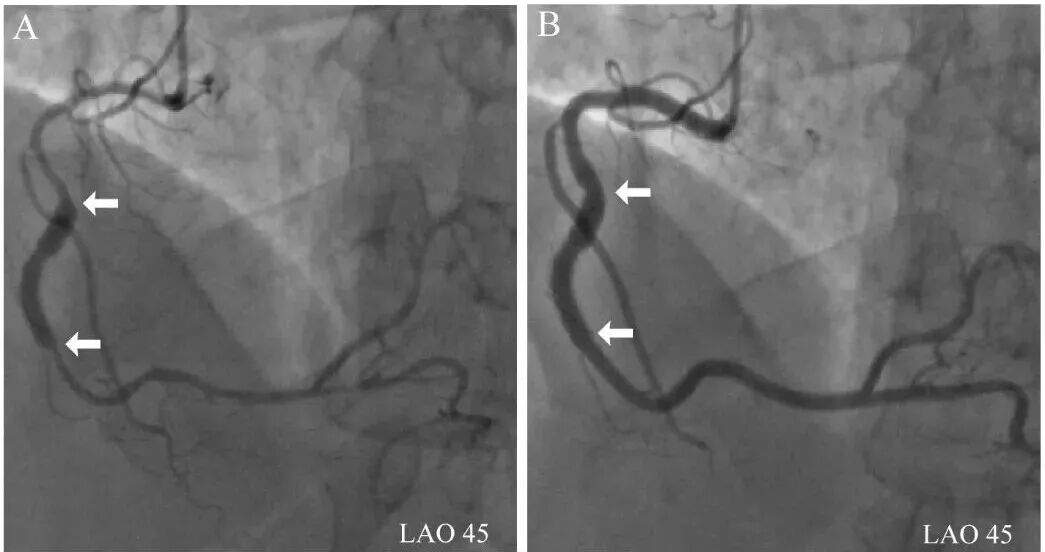

图7 右冠中段支架突兀提示冠脉痉挛。

整个右冠血管弥漫变细,中段支架“突兀和过大”(A),冠脉内注射硝酸甘油后血管明显增粗(B)!箭头所示为支架两端。